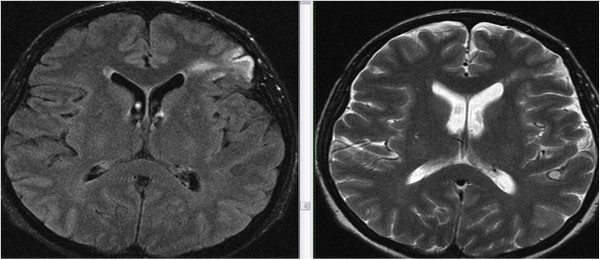

Основной метод, позволяющий обнаружить глиоз головного мозга — нейровизуализация.

Для этого используется компьютерная и магнитно-резонансная томография. При этом в участках белого вещества будут наблюдаться затемнения.

Диагностировать нарушения с достаточной точностью может лишь магнитно-резонансная томография.

Метод позволяет четко определить объем изменения и его локализацию, а, значит, уточнить или установить настоящие причины поражения, так как локализация очагов в отличие от симптомов специфична.

- МРТ – наиболее информативный метод. Он дает понятие об объемах, локализации глиальных очагов, определяет их этиологию. Только с помощью этой методики диагностируют субкортикальные очаги, локализованные в лобных долях мозга, микроангиопатию – мельчайшие повреждения сосудов, зоны перифокального отека.